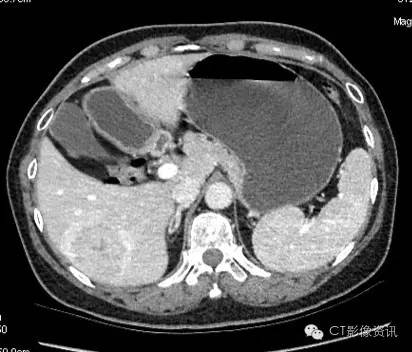

病史 女性,57岁,体检发现肝脏病灶,为明确病灶性质行CT增强检查。

各期扫描及CT值测定 平扫

病灶内CT值:55.13

动脉期

病灶内CT值:160.26

静脉期

病灶内CT值:144.22